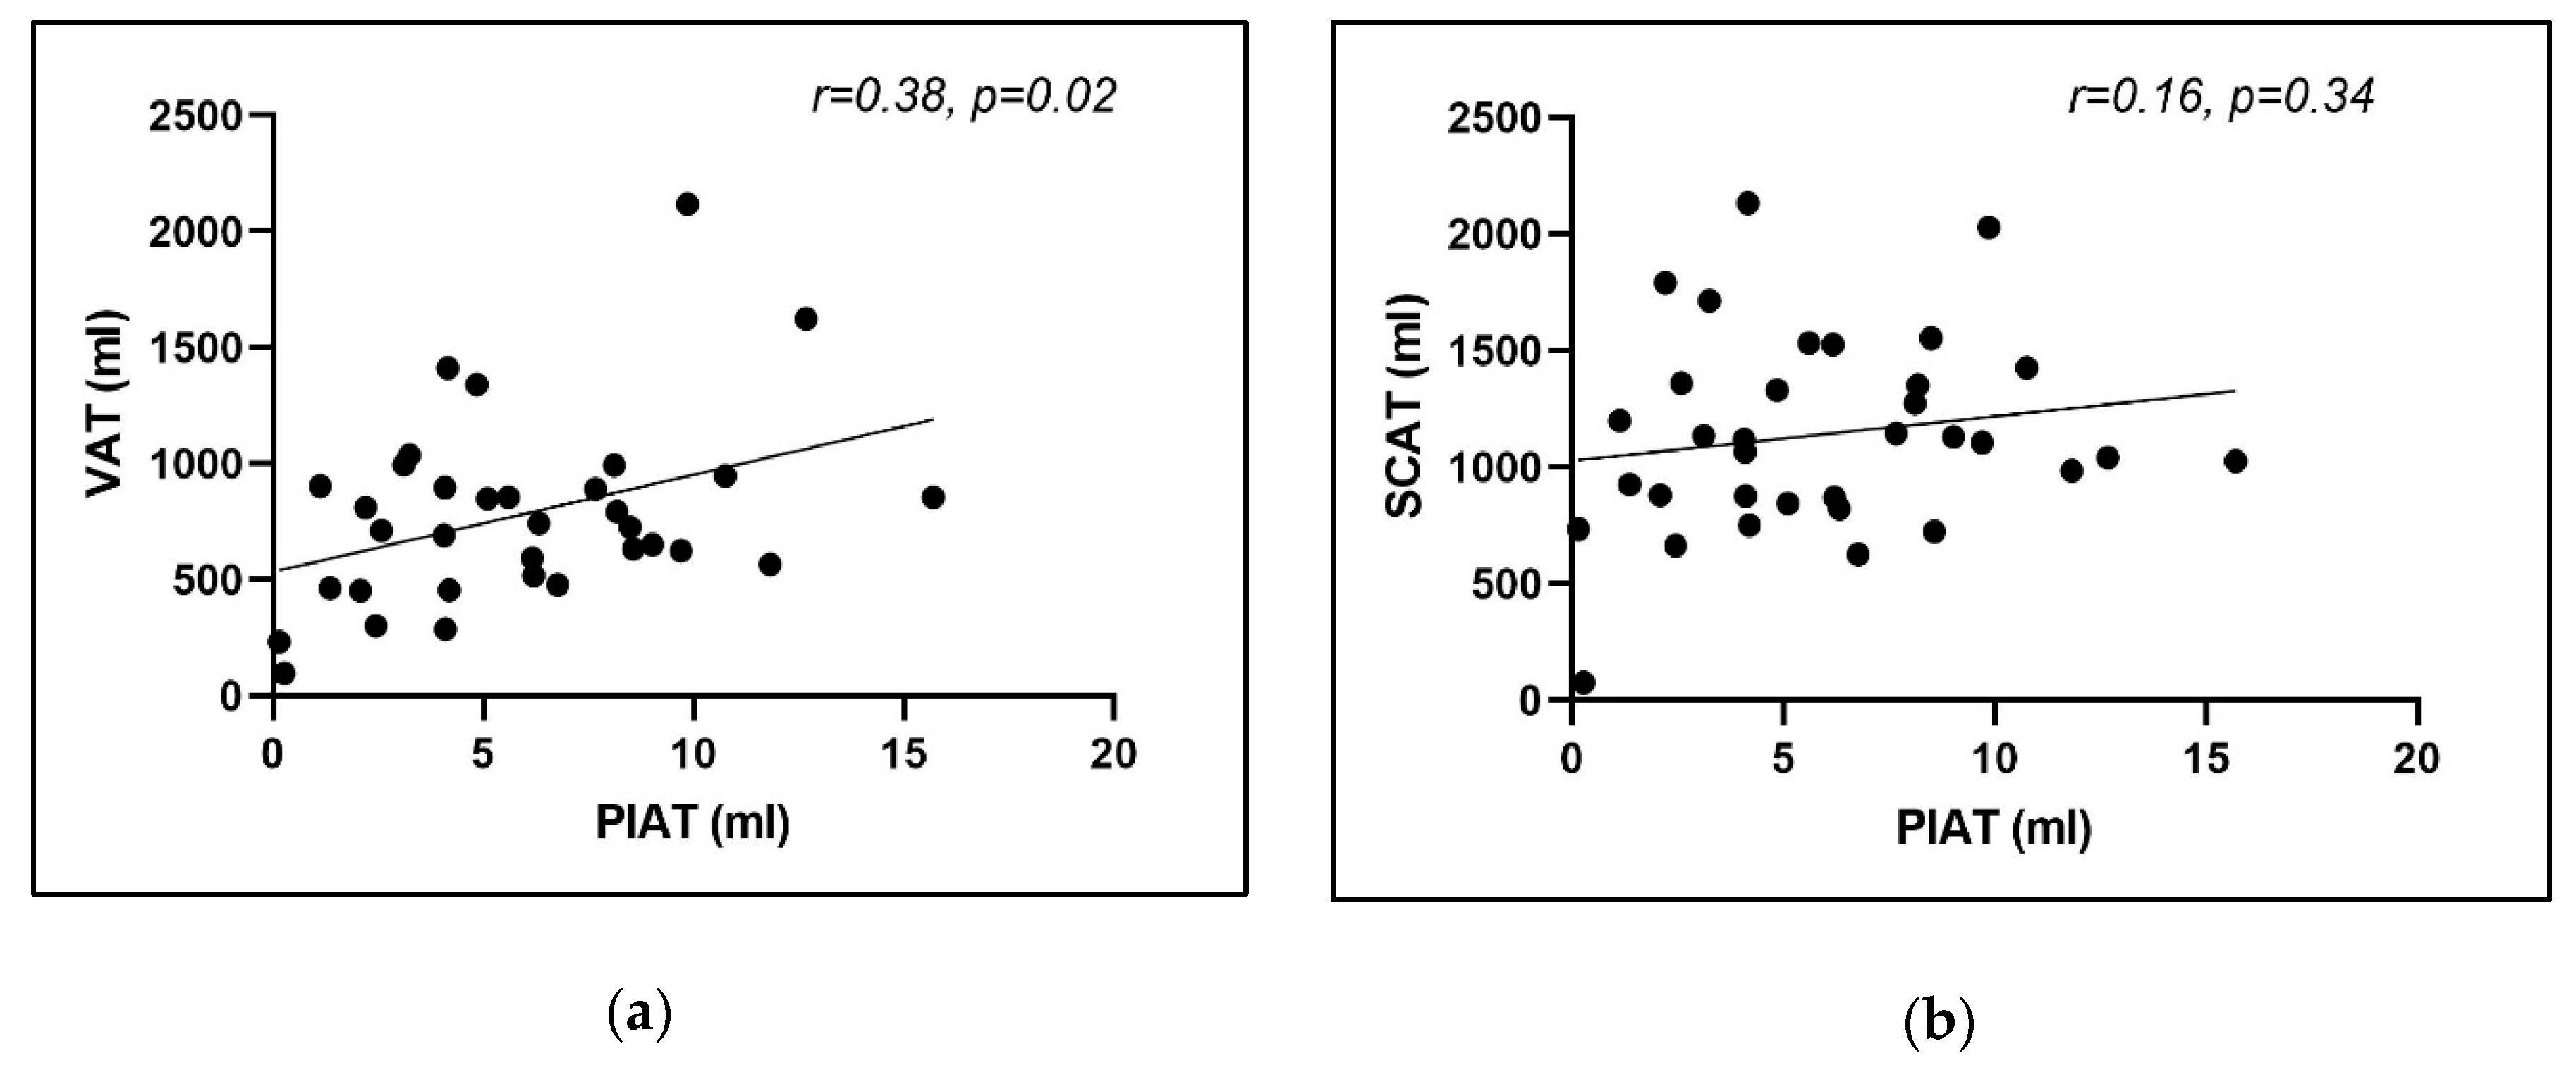

3.3. Computer-Aided Imaging Biomarkers Characterizing Adipose Tissue Distribution